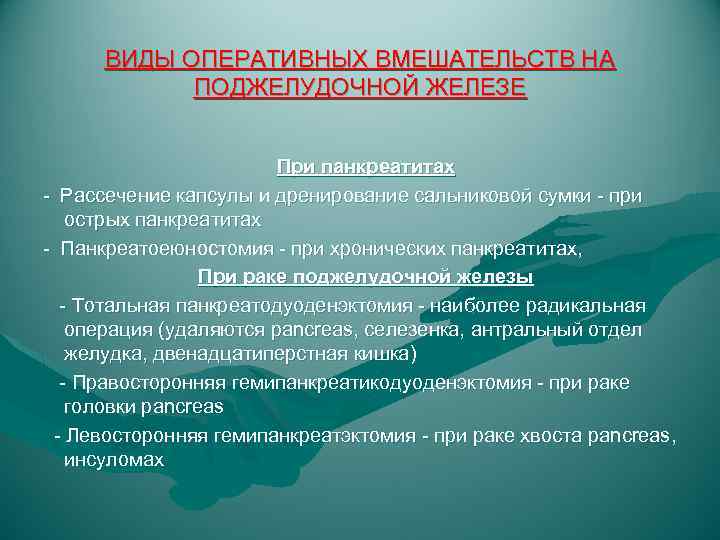

ВИДЫ ОПЕРАТИВНЫХ ВМЕШАТЕЛЬСТВ НА ПОДЖЕЛУДОЧНОЙ ЖЕЛЕЗЕ При панкреатитах - Рассечение капсулы и дренирование сальниковой сумки - при острых панкреатитах - Панкреатоеюностомия - при хронических панкреатитах, При раке поджелудочной железы - Тотальная панкреатодуоденэктомия - наиболее радикальная операция (удаляются pancreas, селезенка, антральный отдел желудка, двенадцатиперстная кишка) - Правосторонняя гемипанкреатикодуоденэктомия - при раке головки pancreas - Левосторонняя гемипанкреатэктомия - при раке хвоста pancreas, инсуломах

ВИДЫ ОПЕРАТИВНЫХ ВМЕШАТЕЛЬСТВ НА ПОДЖЕЛУДОЧНОЙ ЖЕЛЕЗЕ При панкреатитах - Рассечение капсулы и дренирование сальниковой сумки - при острых панкреатитах - Панкреатоеюностомия - при хронических панкреатитах, При раке поджелудочной железы - Тотальная панкреатодуоденэктомия - наиболее радикальная операция (удаляются pancreas, селезенка, антральный отдел желудка, двенадцатиперстная кишка) - Правосторонняя гемипанкреатикодуоденэктомия - при раке головки pancreas - Левосторонняя гемипанкреатэктомия - при раке хвоста pancreas, инсуломах